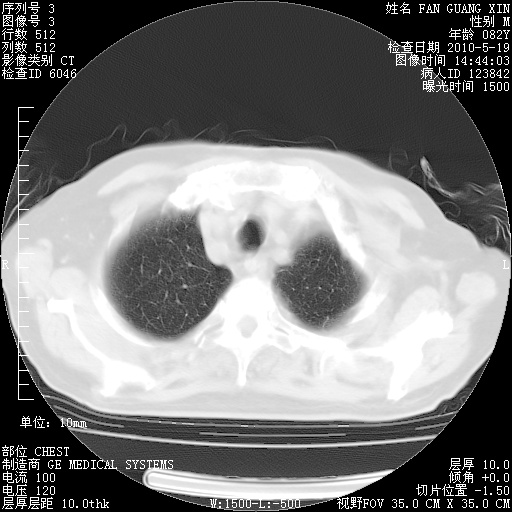

复查肺部CT,明显好转。为什么发热呢?

治疗3周后的肺部CT